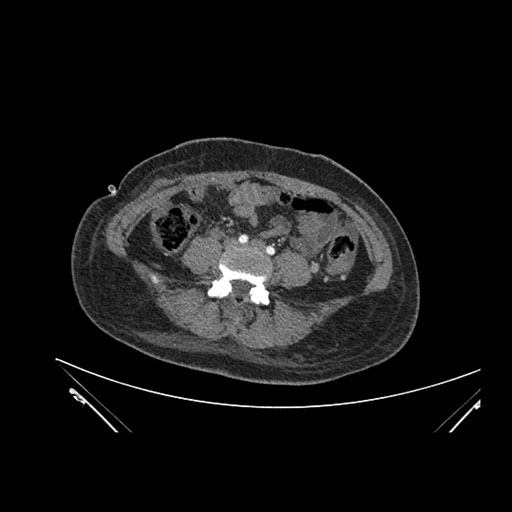

Axial Venous